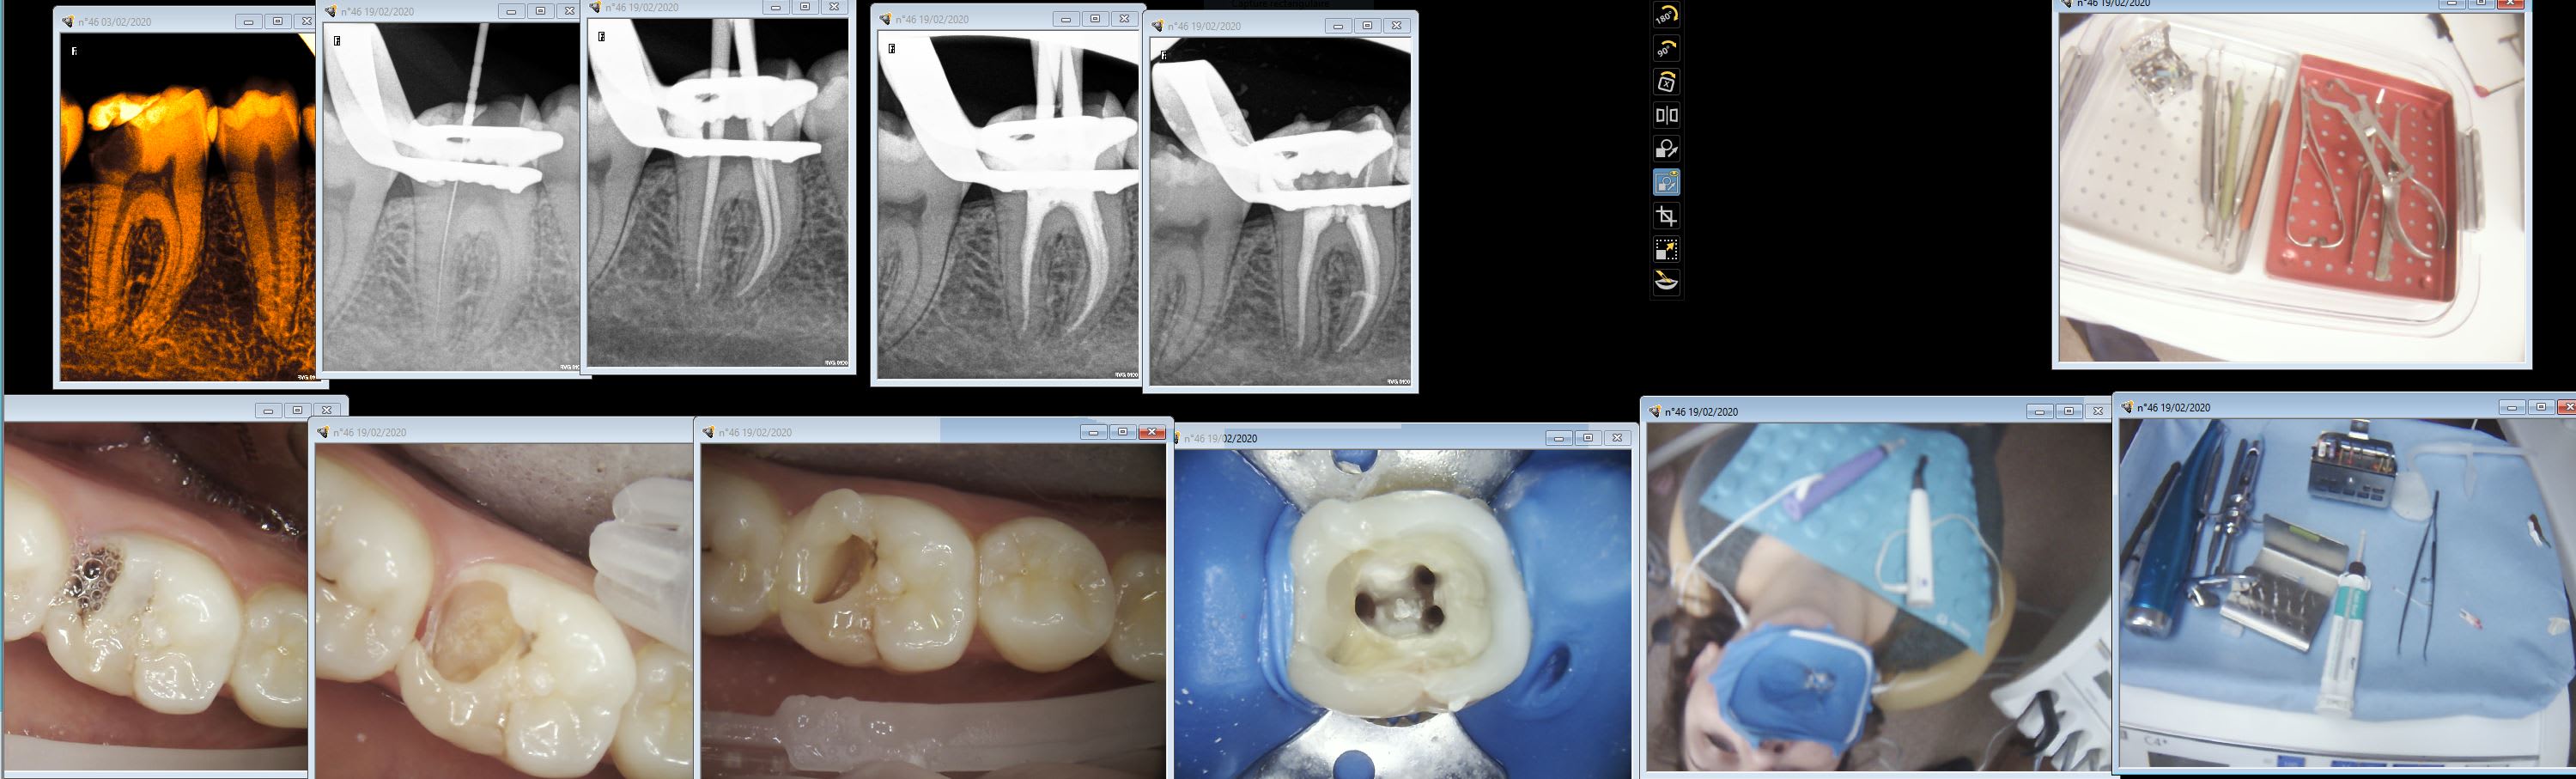

A chier. Fanta endo blue s one 25-04 et 25-06 450 tours 2,6 de couple sur motopex le tout chinetok. Terminé en 2 coups de cuillère à pot.

Tu vois ca coule pas le compo fluide. RCPE Luxacore pred sans matrice. -)))

Et non la patiente n'écoute pas de la musique en stéréo. -)))

Tu fais pas ça avec un eddy. Ta solution d'irrigation t'en as plus dans la cavité en 2 s.